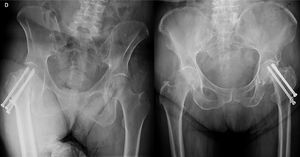

El Femoral Neck System (FNS) (DePuy Synthes®) es una alternativa como método de osteosíntesis en fracturas subcapitales de cadera (fig. 1). Aunque ha demostrado superioridad mecánica sobre los implantes tradicionales en estudios anatómicos, es crucial evaluar la seguridad y establecer los resultados de este nuevo implante en el paciente. Son pocos los estudios que analizan los resultados clínicos tratando de determinar si se trata de una alternativa superior a los TC para manejar fracturas subcapitales de cadera no desplazadas en adultos8–10.

Para los pacientes del grupo TC, se colocaron agujas de Kirschner bajo control fluoroscópico, de manera que formaran un triángulo invertido. Una vez bien posicionadas, se introdujeron tres tornillos canulados de rosca parcial siguiendo la dirección de las agujas para fijar la fractura (fig. 3).

El resto de variables no mostraron diferencias significativas (TC frente FNS): necrosis avascular de la cabeza femoral (fig. 3) (0% frente 11,1%; p=0,391); seudoartrosis cuello femoral (0% frente 20%; p=0,163); dolor inguinal residual (42,9% frente 37,5%, p=0,98); balance articular completo (85,7% frente 87,5%, p=0,98); pérdida hemática o diferencia (medido en niveles de hemoglobina g/dl) previa y posterior a la cirugía (mediana 1,6g/dl frente mediana 1,2g/dl; p=0,571) y presencia de acortamiento del cuello femoral en las radiografías de seguimiento (7,1% frente 11,1%; p=1).